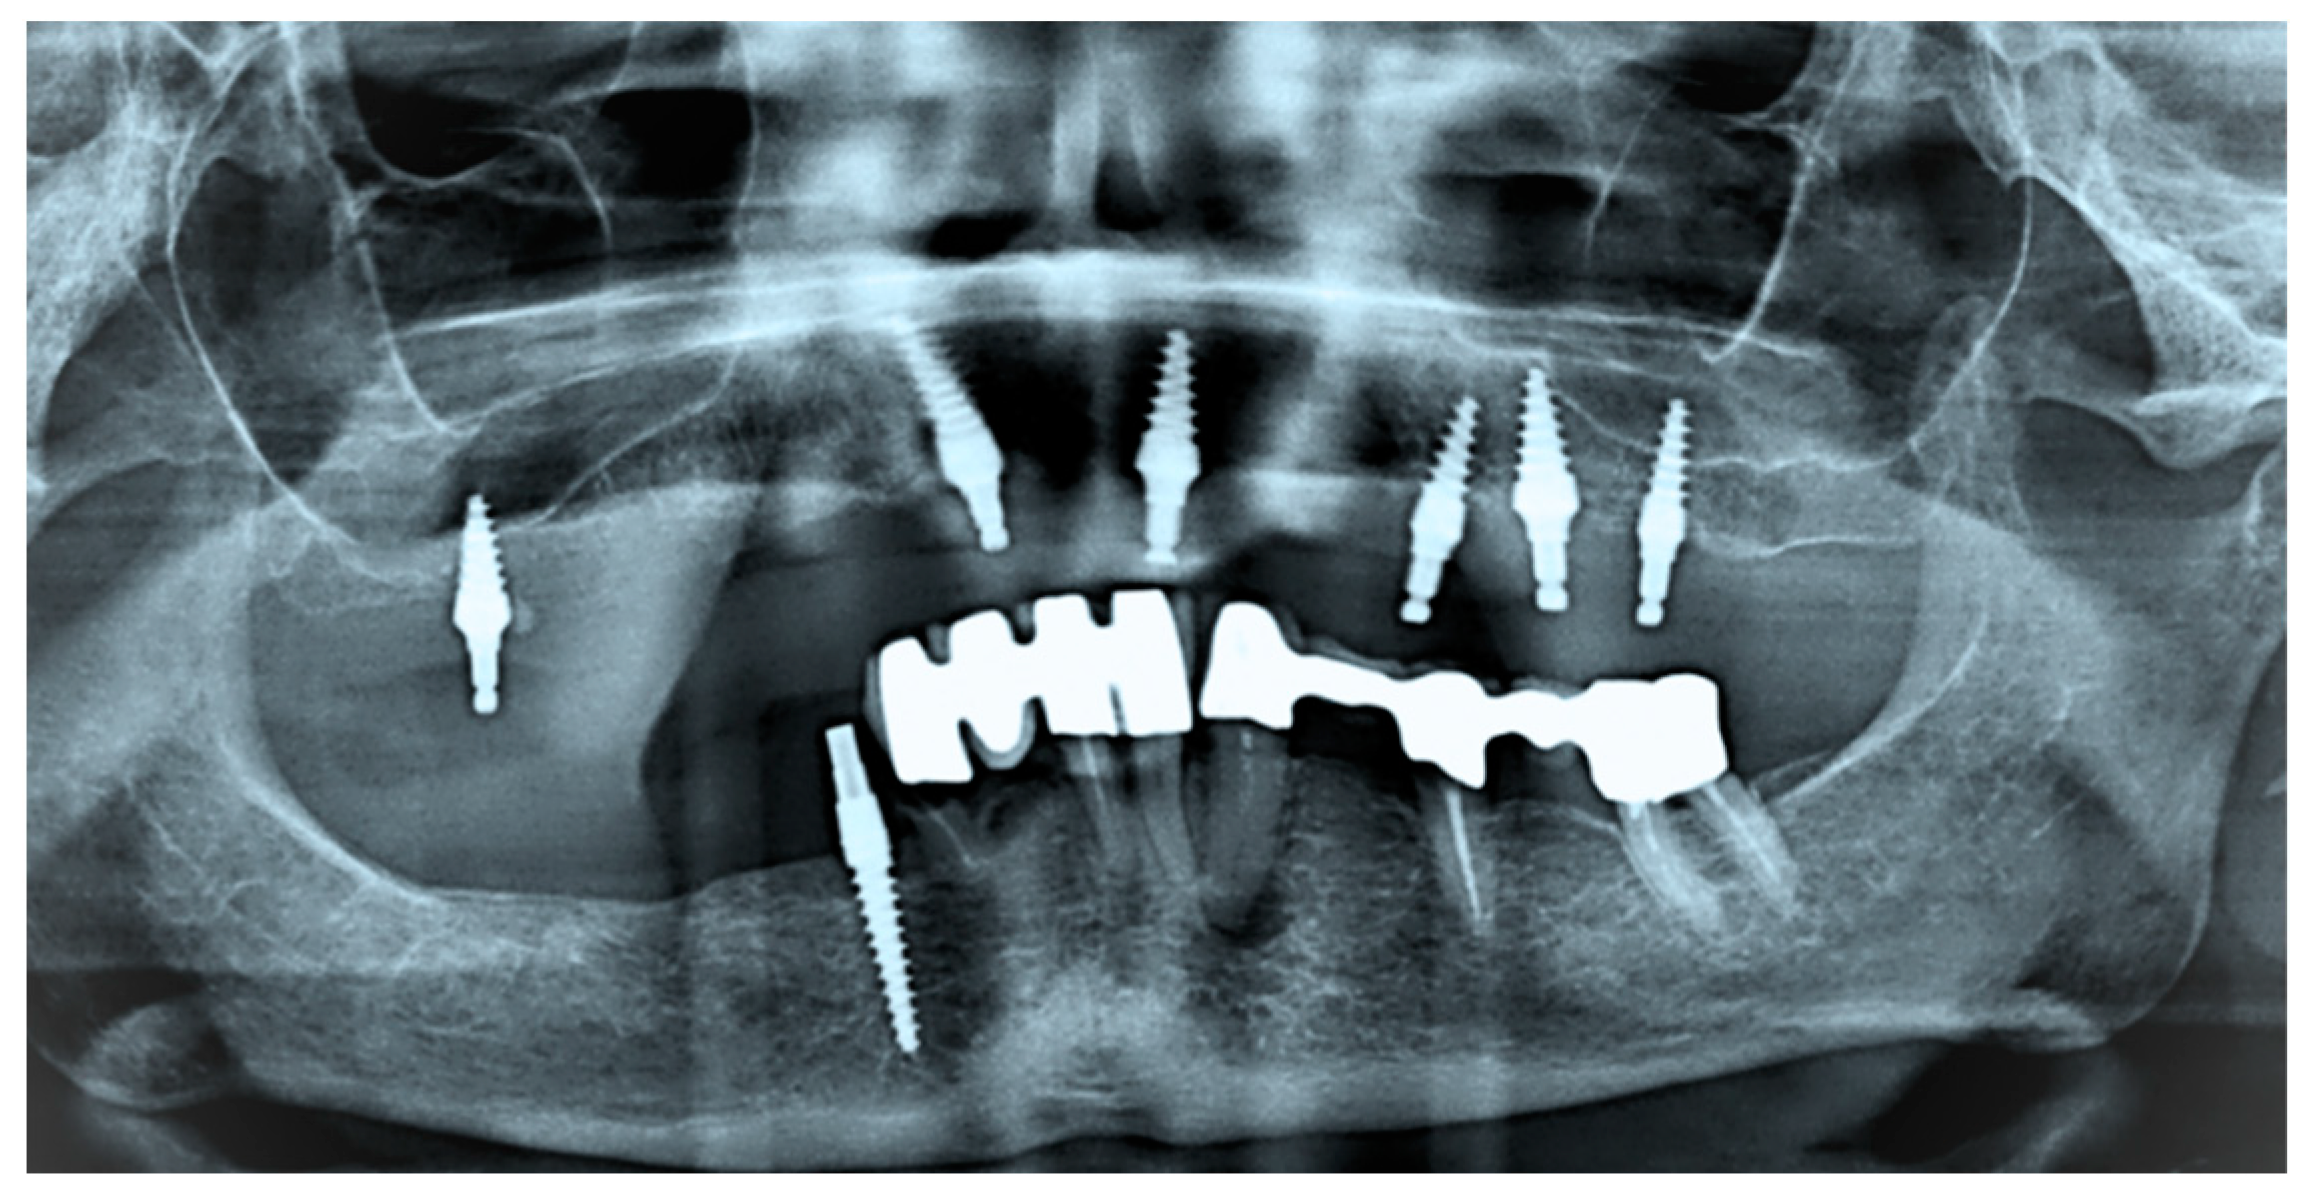

Finite Element Combined Design and Material Optimization Addressing the Wear in Removable Implant Prosthodontics

1. Introduction